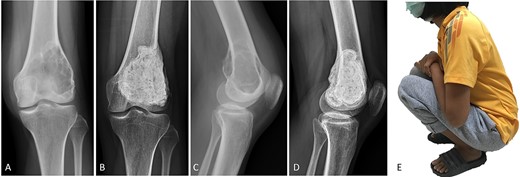

(A, C) Case no. 6: male, 15 years of age with GCTB at the distal femur without subchondral bone involvement, Campanacci grade II. (B, D) Radiograph at 67 months after extended curettage with hydrogen peroxide, phenol, and cementation. (E) MSTS score 100%.